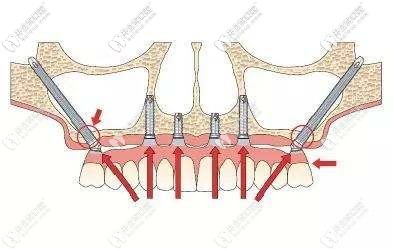

深圳登緹斯口腔的醫(yī)生考慮到我對(duì)傳統(tǒng)種植牙技術(shù)的擔(dān)憂,就對(duì)我的牙槽骨情況做了詳細(xì)分析,建議上頜采用雙側(cè)穿顴穿翼板種植、即刻修復(fù)即刻負(fù)重技術(shù),不用植骨、縮短療程;下頜采用即拔即種的即刻負(fù)重種植技術(shù)。

深圳登緹斯口腔的醫(yī)生還介紹了什么是穿翼板種植牙技術(shù):

穿翼板穿顴種植適用上頜骨萎縮,做常規(guī)種植牙需要植骨、做內(nèi)外提升的無牙頜顧客;而且此技術(shù)無需全麻、手術(shù)不翻瓣、創(chuàng)傷小、術(shù)后腫脹和疼痛也非常輕。